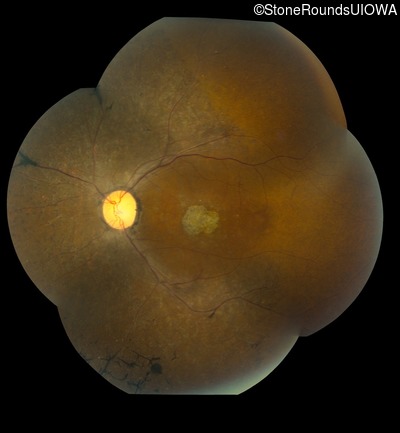

This 47 year old woman was born with a supernumerary digit on the ulnar side of both hands. As a young child, her best corrected visual acuity was completely normal. She had no difficulties with her vision until age 30 when her visual acuity could no longer be corrected to 20/20 and she began to notice some night blindness.

The clinical features supporting the diagnosis of Bardet Biedl syndrome in this patient include: bone-spicule-like pigmentation, narrowed arterioles and macular atrophy on ophthalmoscopy; photoreceptor loss on OCT; ulnar polydactyly, obesity, abnormal cognition, hypertension; and, normally sighted parents.